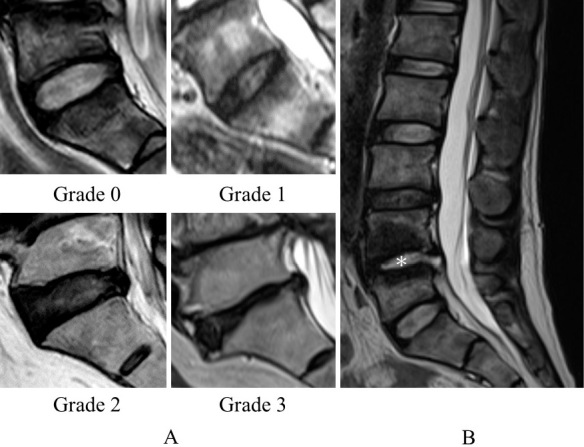

Methods: A total of 85 patients with lumbar pyogenic spondylitis (the infected group) and 156 with lumbar spondylosis who underwent posterior lumbar interbody fusion (the noninfected group) were retrospectively evaluated. Patients with a previous history of spinal fusion, tuberculous spondylitis, and multilevel infection and those receiving dialysis were excluded. Magnetic resonance imaging of the lumbar spine was conducted. Each disc at the L1/2-L5/S levels was graded. The total score of the four discs, excluding the affected disc, was used as the modified disc degenerative disease (DDD) score. Propensity score matching was performed using independent variables such as age, sex, diabetes mellitus, cancer, and steroid use. The modified DDD scores at all and each disc level were compared between the two matched groups.